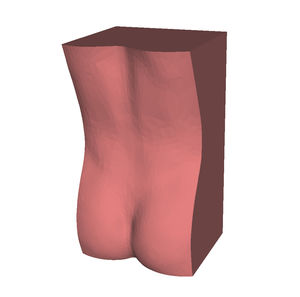

Anatomisches Modell / Schulter HUM-Efür Punktionenfür Injektionenfür Ultraschalluntersuchungen

- Körperteil

- Schulter

- Farbe

- rosa

Echogene und röntgendichte anatomische Schaufensterpuppen

für eine bessere Ausbildung in interventionellen Verfahren unter Ultraschall und Röntgenstrahlen

Identifizierung anatomischer Orientierungspunkte mit Ultraschall und Röntgenstrahlen

Training für Punktion und Infiltration unter Ultraschall und Röntgenstrahlen

Hautgetreues Stichempfinden mittels Echo und Radio

Alle unsere Schaufensterpuppen sind echogen und röntgendicht und können bis zu 600 Injektionen pro Stelle tragen.